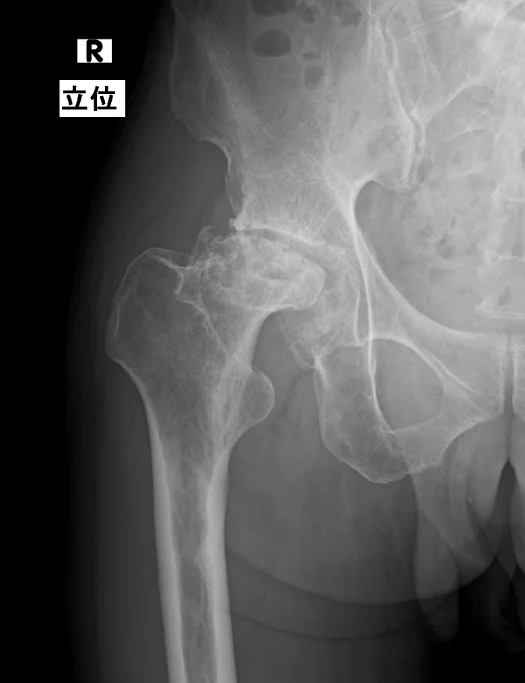

時間の経過とともに関節の隙間(関節裂隙)の急速な狭まりや、大腿骨頭(ももの骨)の一部消失・陥没、寛骨臼(骨盤側の受け皿)の破壊がレントゲンで確認できるようになります。

特徴的なのは、通常の変形性股関節症に見られる骨棘(余分な骨のとげ)形成などがほとんど見られません。

具体的な診断基準としては、「1年間で関節の隙間が50%以上消失」あるいは「大腿骨頭の高さが2mm以上失われる」といった定義が提唱されています。